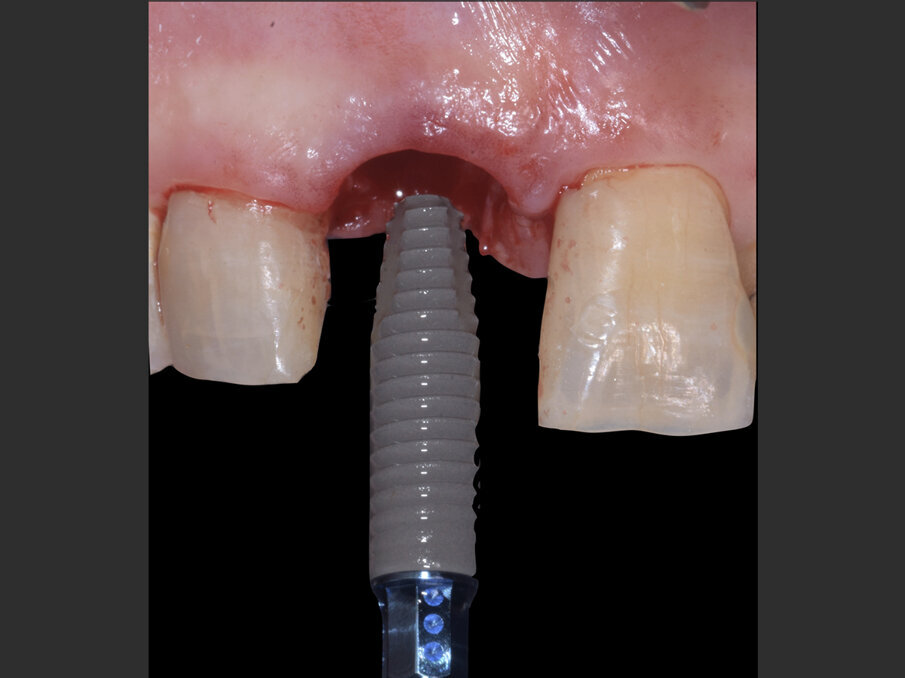

Il giorno dell’intervento, dopo somministrazione locale di articaina al 4% e adrenalina 1:100.000, l’elemento viene lussato delicatamente mantenendo integri i tessuti molli tramite l’uso di periotomi dedicati (Carda #2 e Carda #3 - Omnia) ed estratto. L’alveolo viene curettato e deterso con soluzione salina, e il tessuto epiteliale sulculare viene rimosso con una lama 15c, così da esporre il sottostante tessuto connettivale. Viene preparata un’osteotomia calibrata con frese dedicate, così da ingaggiare l’apice implantare (BLT Bone Level Tapered Roxolid SLActive, Straumann 4.1x14 mm) nel triangolo osseo apicale e palatale all’apice alveolare e posizionare il profilo coronale dell’impianto 1 mm al di sotto del margine della cresta vestibolare. Dopo il posizionamento implantare, con l’ausilio di un compattatore d’osso conico (Carda #4 - Omnia), il gap residuo vestibolare viene colmato con osso bovino deproteinizzato (Geistlich Bio-oss Collagen 50 mg, Geistlich) così da assicurare un perfetto riempimento tridimensionale dell’alveolo residuo. L’impianto viene infine posizionato con un torque di 50 N/cm (Figg. 3, 4a, 4b).

Fig. 3 - Straumann BLT Roxolid SLActive RC 4.1 x 14 mm.

Fig. 4a - Impianto inserito lontano dalla corticale ossea vestibolare in modo da creare un gap superiore a 2 mm.

Fig. 4b - Il jumping space tra impianto e corticale ossee viene colmato con Geistlich BioOss Collagen.